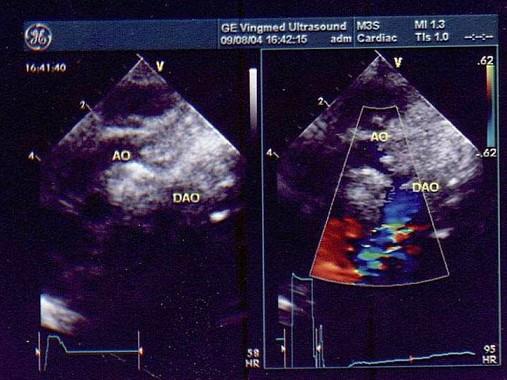

两个月患儿如图所示,该病例诊断最可能是?(?)A.主动脉弓扩张B.主动脉弓狭窄C.升主动脉扩张D.主动脉粥样斑块E.以上都不是

问题 两个月患儿如图所示,该病例诊断最可能是?(?)

选项 A.主动脉弓扩张 B.主动脉弓狭窄 C.升主动脉扩张 D.主动脉粥样斑块 E.以上都不是

答案 B